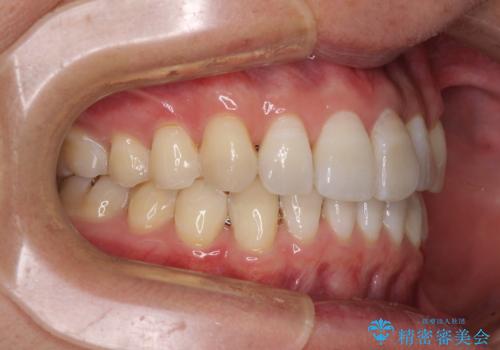

前歯のデコボコを治したい インビザラインによる矯正治療

- 前歯のデコボコを治したいとのことで来院された患者様です。

上下顎ともに歯列全体の後方移動とIPR(歯と歯の間を削る)によってデコボコが解消するように設計し、インビザラインにより治療を行うこととしました。

矯正治療後、前歯の形と色が気になるとのことでしたが、大分前に失活している(神経が取り除かれている)歯であり、その影響で変色しているため、オールセラミッククラウンによる補綴治療をおすすめいたしました。